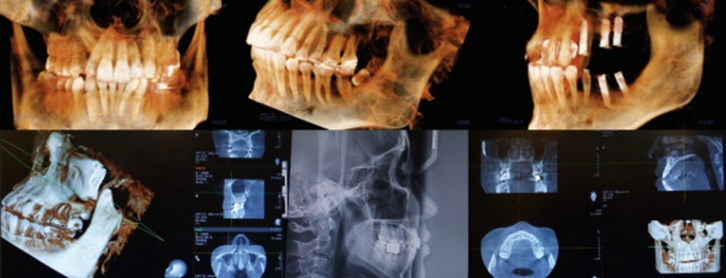

기존의 평면적이었던 X-ray나 파노라마 보다 더 정확하고 더 정밀한

3D CT를 이용하여 치아 뿌리의 상태, 위치, 이동 가능량, 잇몸뼈 등

치아와 잇몸 상태 뿐만 아니라 얼굴 골격까지 진단하여 오차없고 섬세한 치료계획을 수립합니다.

3D구강스캐너와 CBCT등을 통해 수집한 데이터를 토대로

치아 뿌리의 특성, 얼굴의 골격, 비대칭 정도, 치아의 이동 예측량, 치아의 교합을 꼼꼼하게 분석하고

교정의 치료 결과예측을 위해 삼차원적으로 시뮬레이션하여 오차 없는 치료 계획을 수립합니다.

임플란트 수술 전 3D CT를 분석하여 모의 수술하게 되며,

골조직과 신경의 위치를 정확하게 파악하고 시뮬레이션 함으로써

신경손상 가능성이 전무하며 미리 계획된 방향과 위치에 임플란트를 식립할 수 있습니다.